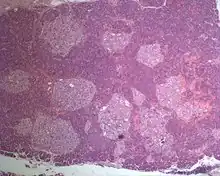

Photographic image of the numerous islets of various sizes in the pancreas of a patient with Mahvash disease

Most patients with Mahvash disease are diagnosed in adulthood. Patients with Mahvash disease usually present with vague abdominal discomfort. Imaging with CT or MRI identifies a very large pancreas with one or more tumors. Biochemical testing shows marked hyperglucagonemia (hundreds-fold elevated). If the tumors are resected, they are found to be neuroendocrine tumors that usually express glucagon. In the tumor margin, pancreatic alpha cell hyperplasia is pervasive, numerous large islets composed of mostly alpha cells are evident, and multiple microadenomas and small neuroendocrine tumors often are present. The pancreatic neuroendocrine tumors are the main health concern for patients with Mahvash disease. Although the tumors commonly are indolent, death due to liver metastasis has been reported.[3] In patients with complete loss of glucagon receptor function, Mahvash disease can present at younger age with portal hypertension and hepatic encephalopathy.[11]